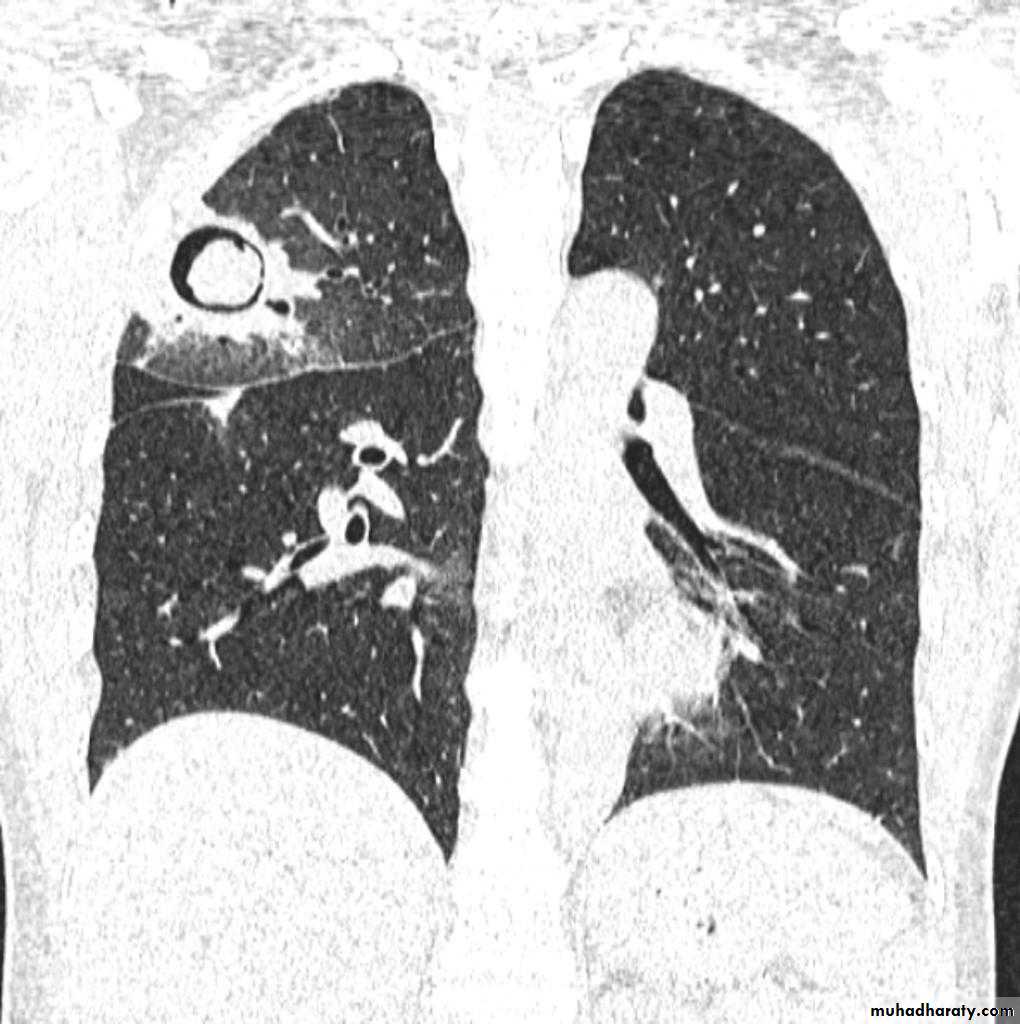

Q ???? Be careful in description & DxBoth of them have similar appearance of broncho pneumonic shadow

??????What is being the pit fall in such films ???

Who can you differentiate ???

62.Q??? Film

63.Q assessment

64.answer this film of Broncho pneumonic (lobular pneumonia ) VS upper zone apical Broncho pneumonic shadow due to post primary TB